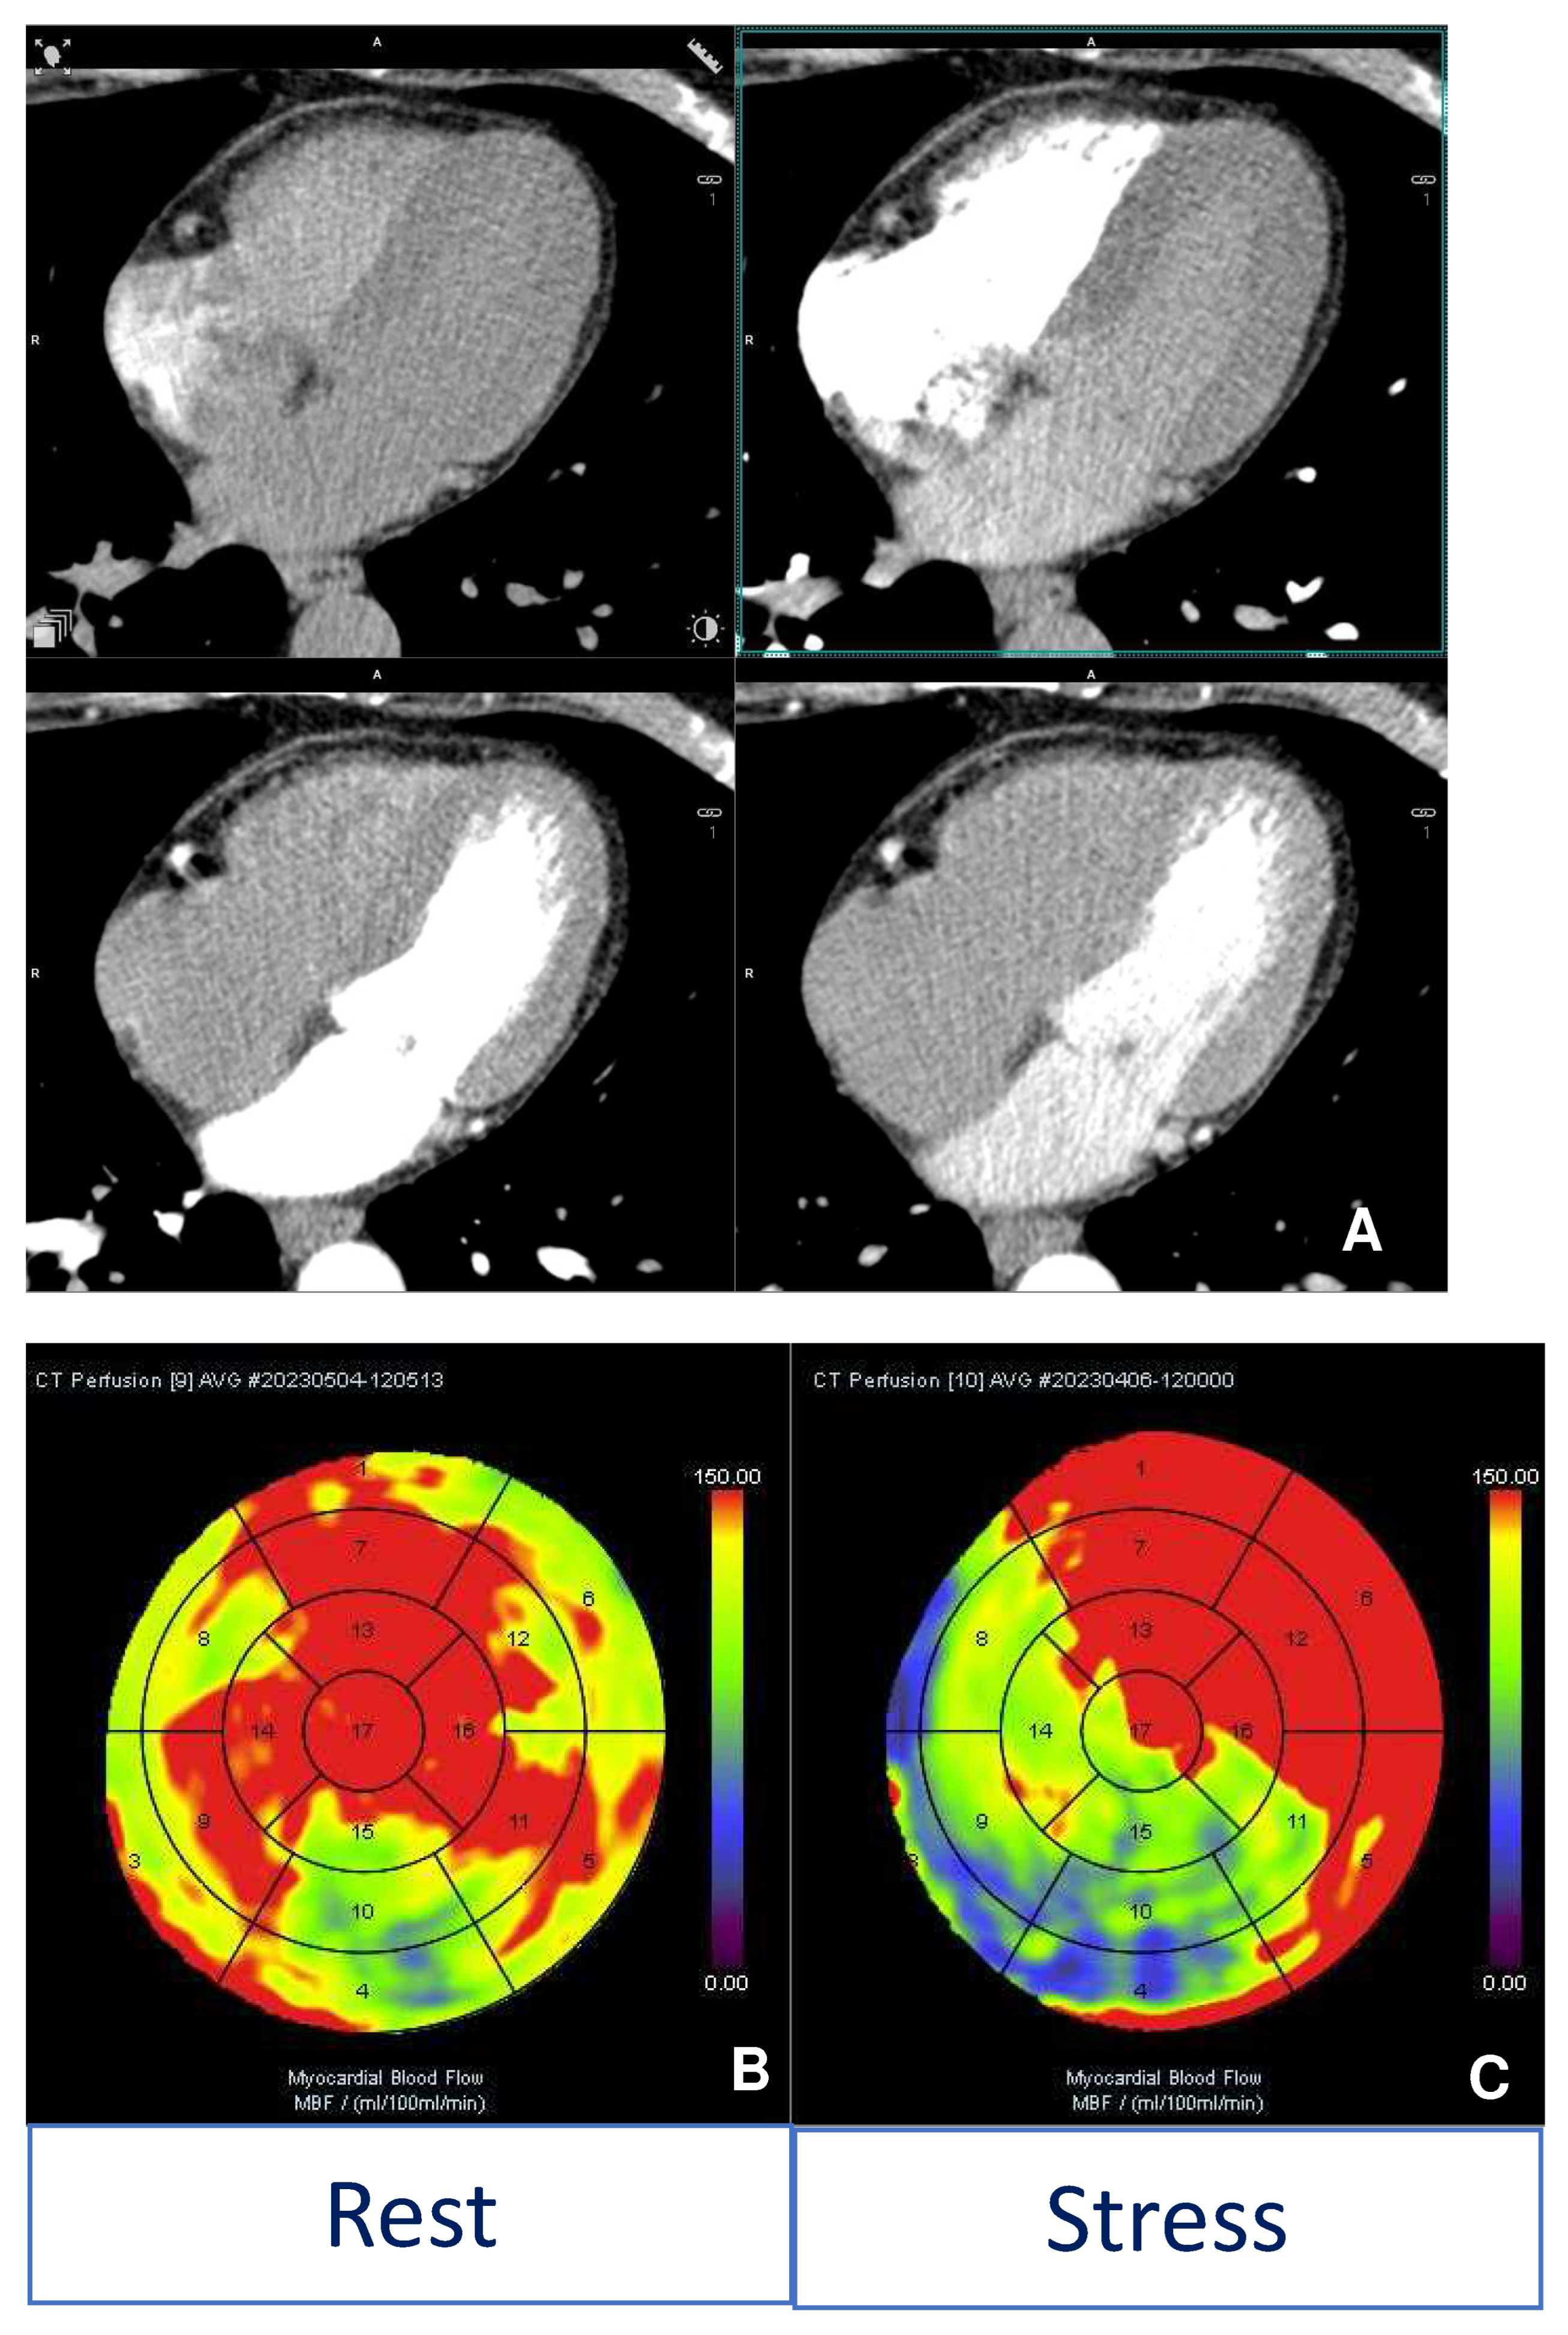

- Hulten, E.; Ahmadi, A.; Blankstein, R. CT Assessment of Myocardial Perfusion and Fractional Flow Reserve. Prog. Cardiovasc. Dis. 2015, 57, 623–631. [Google Scholar] [CrossRef] [PubMed]

- Kim, M.Y.; Yang, D.H.; Choo, K.S.; Lee, W. Beyond Coronary CT Angiography: CT Fractional Flow Reserve and Perfusion. J. Korean Soc. Radiol. 2022, 83, 3–27. [Google Scholar] [CrossRef] [PubMed]

- Coenen, A.; Rossi, A.; Lubbers, M.M.; Kurata, A.; Kono, A.K.; Chelu, R.G.; Segreto, S.; Dijkshoorn, M.L.; Wragg, A.; van Geuns, R.-J.M.; et al. Integrating CT Myocardial Perfusion and CT-FFR in the Work-Up of Coronary Artery Disease. JACC Cardiovasc. Imaging 2017, 10, 760–770. [Google Scholar] [CrossRef] [PubMed]